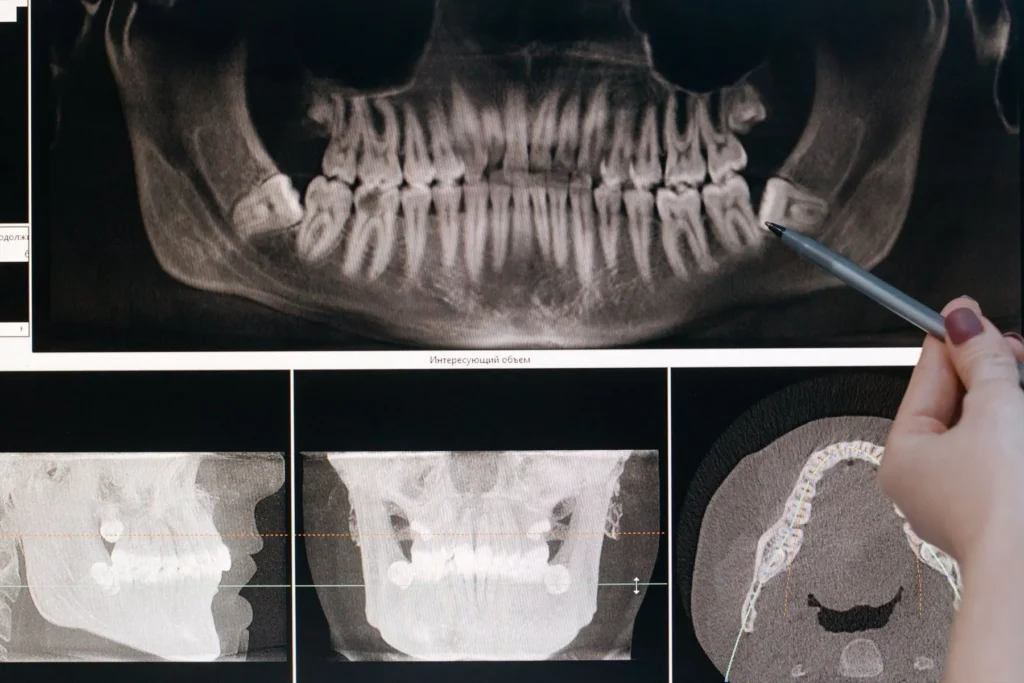

Radiografias dentais

Radiografias dentais Raios-X dentais podem detectar problemas logo no início em sua boca, dentes, gengivas e osso da maxila e mandíbula. Tratar os problemas antes que se tornem sérios pode economizar dinheiro, dor e, às vezes, até sua vida. O que são raios-X dentais e por que são necessários? Na lista de suas coisas favoritas, […]